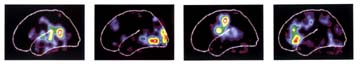

Genética, llave para las

enfermedades humanas